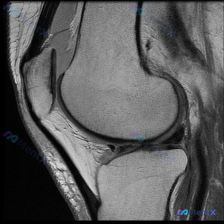

刚整理完这份膝关节MRI的读片思路,这个病例其实挺有代表性,很容易犯锚定错误,分享给大家一起看看。 病例基本影像信息 本次提供的是膝关节MRI矢状位T2加权图像,具体影像学发现如下: 1. 骨骼结构:股骨远端髁前部及滑车无明显骨折,胫骨平台关节面完整无塌陷,髌骨结构未见明显异常;股骨远端周围皮下软组...